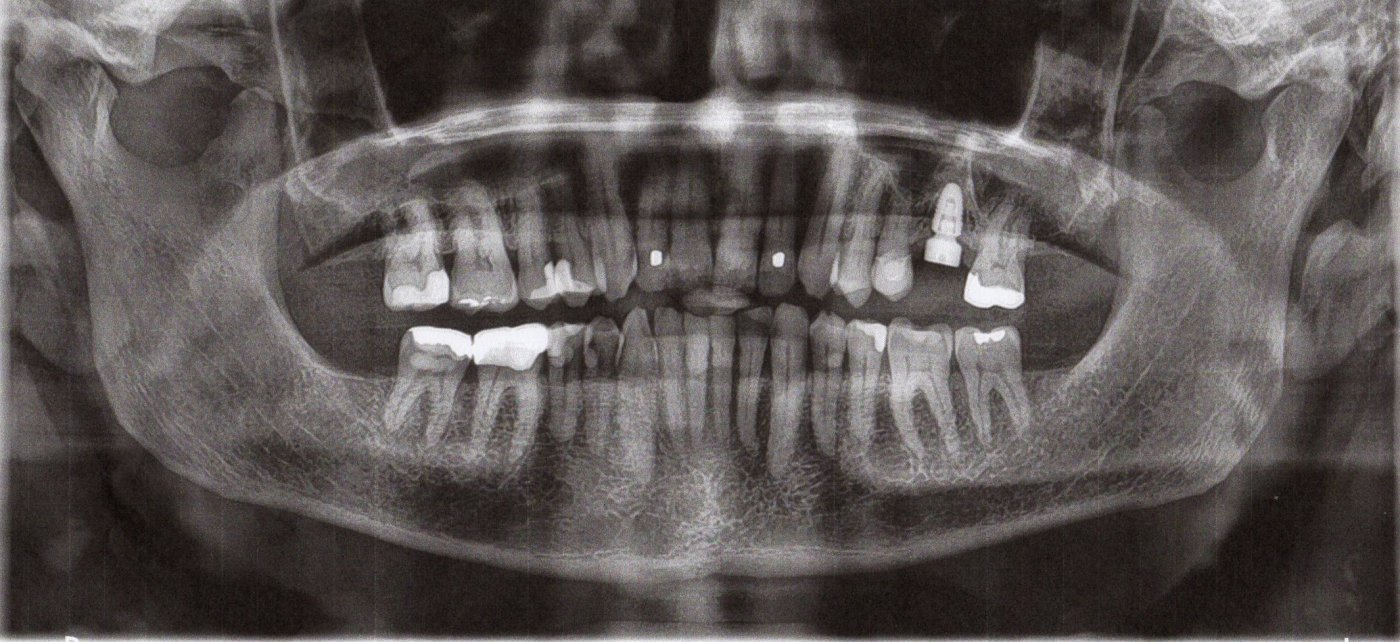

Today I received my first-ever dental implant. See the photo. It’s #14, top left (your right) second from last molar.

I won’t go into details about the procedure, except to say the ratchet wrench was kind of a surprise. The bill was not a surprise. They x-rayed my wallet ahead of time to make sure I could pay it.